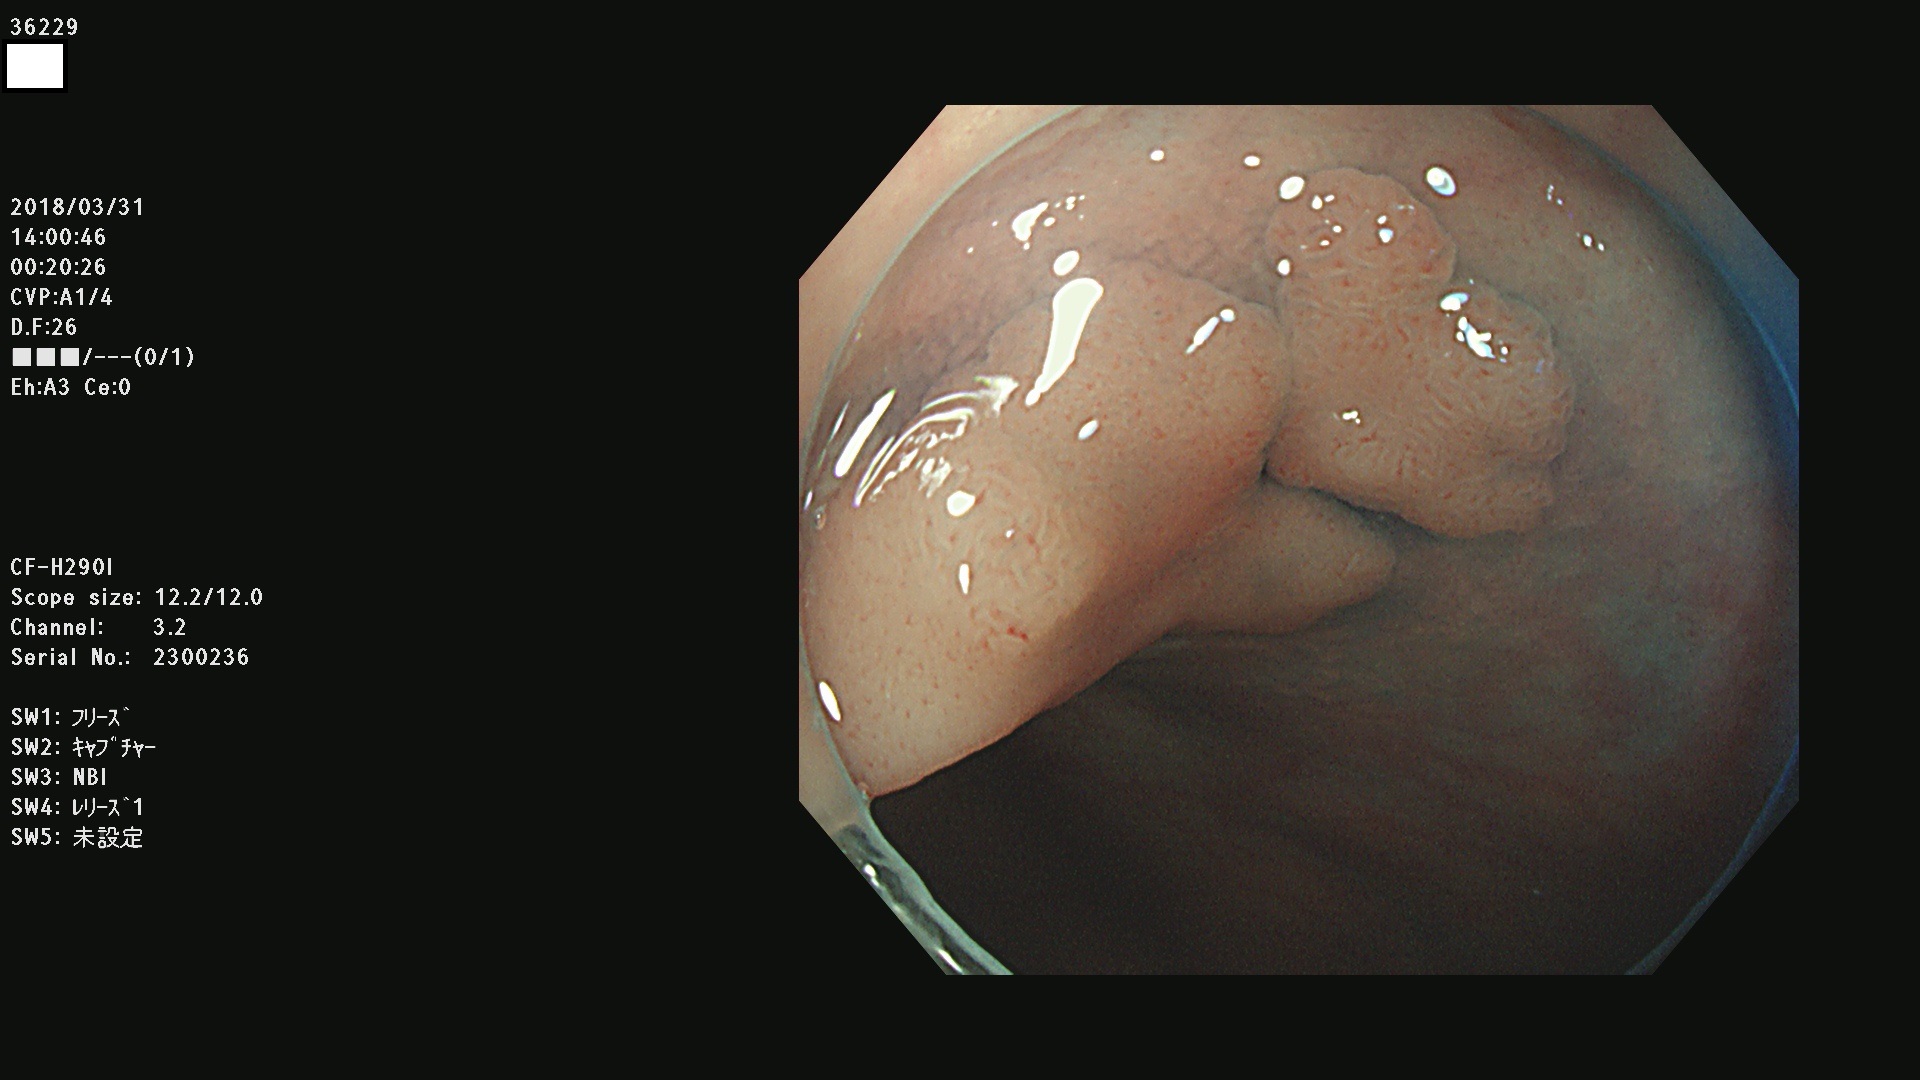

発見困難で危険性の高い平坦型病変(上記100名より抽出)

36201 36202 36203 36205 36207 36209 36210 36212 36213 36214 36215 36217 36220 36221 36222 36224 36225 36226 36227 36229 36230 36231 36232 36235 36236 36238 36240 36243 36244 36246 36247(SSAPのみ。SPS) 36248 36249 36251 36252 36253 36254 36255 36256 36257 36258 36259 36261 36262 36264 36265 36267 36269 36270 36272 36274 36275 36276 36279 36280 36281 36283 36285 36288 36289 36291 36292 36295 36296 36297 36299